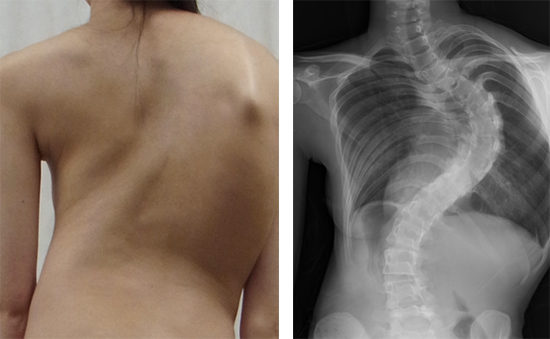

側彎とは、背骨が横に曲がった状態をいいます(図1)。ヒトの背骨は完全に真っ直ぐではありませんが、曲がりの角度が10度以上になると病的(側彎症)と考えられています。曲がりの角度が20度を超えると、装具の着用など何らかの治療をする必要が生じ、40度を超えると、多くの場合手術治療が必要となります。さらに重度になった場合は、肺機能が低下し、腰痛や背部痛の発症が増加するとされています。進行すると治療が困難になるので、早期発見が大切です。

図1 側彎症

左:側彎症患者の外観。右:脊椎X線画像(背面図)。背骨が大きく弯曲している。